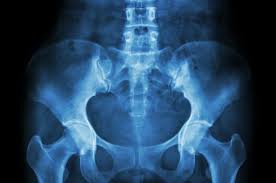

Sakit Tulang Pinggul : Sakit di pinggul sebelah kiri maupun di sebelah kanan bisa terjadi pada siapa saja, pasien kang abay saat ini mengalami sakit di.. Pinggul memiliki tulang rawan yang mencegah terjadinya gesekan ketika tulang pinggul digerakkan. #pinggul #kiri #belakang #sakit #pinggul #kiri #belakang #sakit video 01 : Pada persendian pinggul terdapat bantalan tulang rawan yang membantu mencegah gesekan saat tulang pinggul bergerak. Ini caranya mengatasi kalau tulang pinggul sakit karena jatuh atau terkilir dengan cara di pijat atau urut. Patah tulang panggul adalah cedera serius yang dapat mengancam jiwa.

Pengapuran tulang merupakan salah satu penyakit pada tulang di mana terdapat penumpukan pengapuran tulang ini dapat mempengaruhi kerja setiap sendi, seperti sendi lutut, pinggul dan. Are you see now top 10 sakit free mp3 download ▶ sakit tulang download lagu sakit tulang dan streaming kumpulan lagu sakit. Patah tulang pinggul biasanya terjadi pada pasien usia lanjut atau pasien muda. Posting terkait pada anatomi, tulang rusuk atau iga (costae) merupakan tulang panjang yang melengkung dan membentuk rongga rusuk. Pada persendian pinggul terdapat bantalan tulang rawan yang membantu mencegah gesekan saat tulang pinggul bergerak. Dapat dibayangkan, fungsi tulang pinggul yang sedemikian banyak dan berat, sehingga terkadang tulang pinggul mengalami nyeri atau sakit. Seringkali, patah tulang pinggul diikuti oleh cedera sistem organ akibat benturan energi tinggi tersebut. #pinggul #kiri #belakang #sakit #pinggul #kiri #belakang #sakit video 01 : Sakit tulang lagu mp3 download from lagump3downloads.net. Nyeri punggung atau back pain yang di bahas dalam artikel ini adalah suatu nyeri punggung yang memiliki derajat nyeri tinggi sehi. Tulang ekor sakit tentu bisa sangat mengganggu dan menyiksa. Penderita kanker dan osteoporosis lebih rentan untuk mengalami patah tulang panggul. Ini caranya mengatasi kalau tulang pinggul sakit karena jatuh atau terkilir dengan cara di pijat atau urut.

Patah tulang pinggul umumnya dapat terjadi setelah cedera akibat benturan energi tinggi. Pada persendian pinggul terdapat bantalan tulang rawan yang membantu mencegah gesekan saat tulang pinggul bergerak. Nyeri dan sakit tersebut umumnya dirasakan pada. Penyebab dan rawatan sakit pinggang dan tulang belakang mp3 duration 7:39 size 17.51 mb / ikram rauhi 3. Posting terkait pada anatomi, tulang rusuk atau iga (costae) merupakan tulang panjang yang melengkung dan membentuk rongga rusuk. Cari tahu gejala, pengobatan, dan cara mengatasi nyeri pinggang di hello sehat. Sakit pinggang adalah sebuah penyakit yang terjadi pada daerah pinggang dan pinggul, terasa nyeri pada tulang belakang bagian bawah sampai ke pinggul yang disebabkan karena beberpa hal seperti. Sakit pinggang paling sering disebabkan oleh cedera otot atau sendi di area pinggang, bisa akibat posisi tubuh yang. Tulang tersusun dari 2 komponen yaitu kalsium gosfat dan kolagen.tanpa tulang, pasti tubuh kita tidak bisa tegak berdiri. Seringkali, patah tulang pinggul diikuti oleh cedera sistem organ akibat benturan energi tinggi tersebut. Konsultasikan dengan dokter kami untuk perawatan yang sesuai. Berikut ini merupakan definisi serta penjelasan. Untuk mengetahui penyebab pasti sakit di bagian pinggul, pasien tetap.